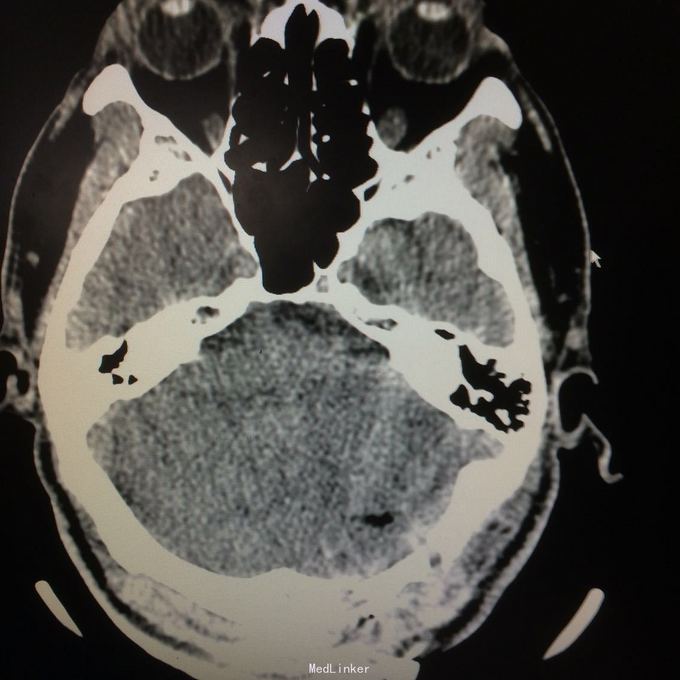

主诉:头晕头痛2年 病史:2年前无明显诱因出现头痛,呈刺痛,程度较重,伴头晕、天旋地转感,1年前查头颅MR提示:左侧小脑半数囊性病变,考虑血管母细胞瘤

查体:神志清楚,病理证阴性 辅助检查:头颅MR提示左侧小脑半数后部囊状占位灶,考虑良性病变。

诊断:左侧小脑血管母细胞瘤 处理:行左侧小脑占位病变切除术,术后病理提示:符合血管母细胞瘤。